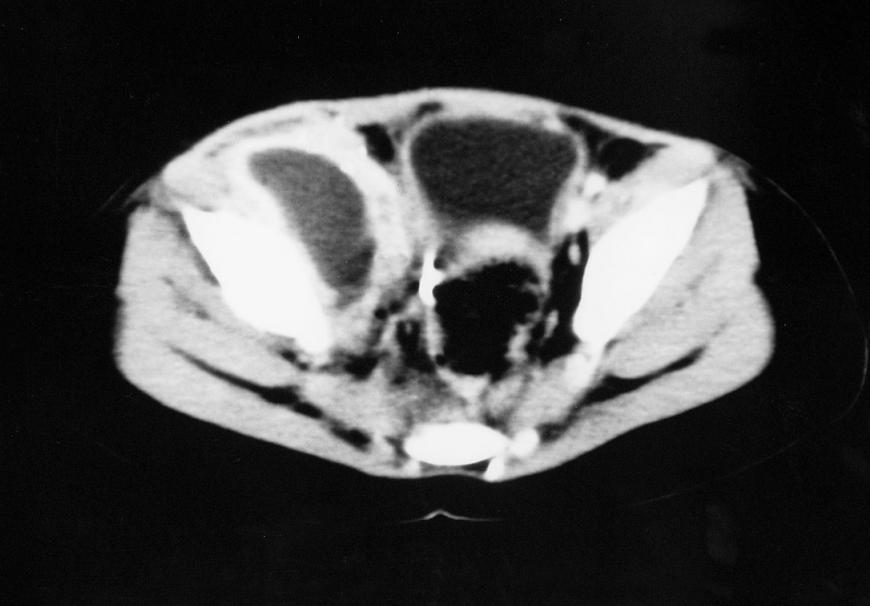

Hip Septic Arthritis Pediatric Pediatrics Orthobullets Septic Arthritis Treatment Orthobullets Though uncommon, septic arthritis is an orthopedic emergency that can cause significant joint damage leading to increased morbidity and mortality. On physical exam, the right knee is erythematous,. Acutely swollen or painful joints are common complaints in the emergency department (ed). Medical history is significant for poorly controlled type ii diabetes mellitus. Acute septic arthritis (sa) in children is most. Septic Arthritis Treatment Orthobullets.